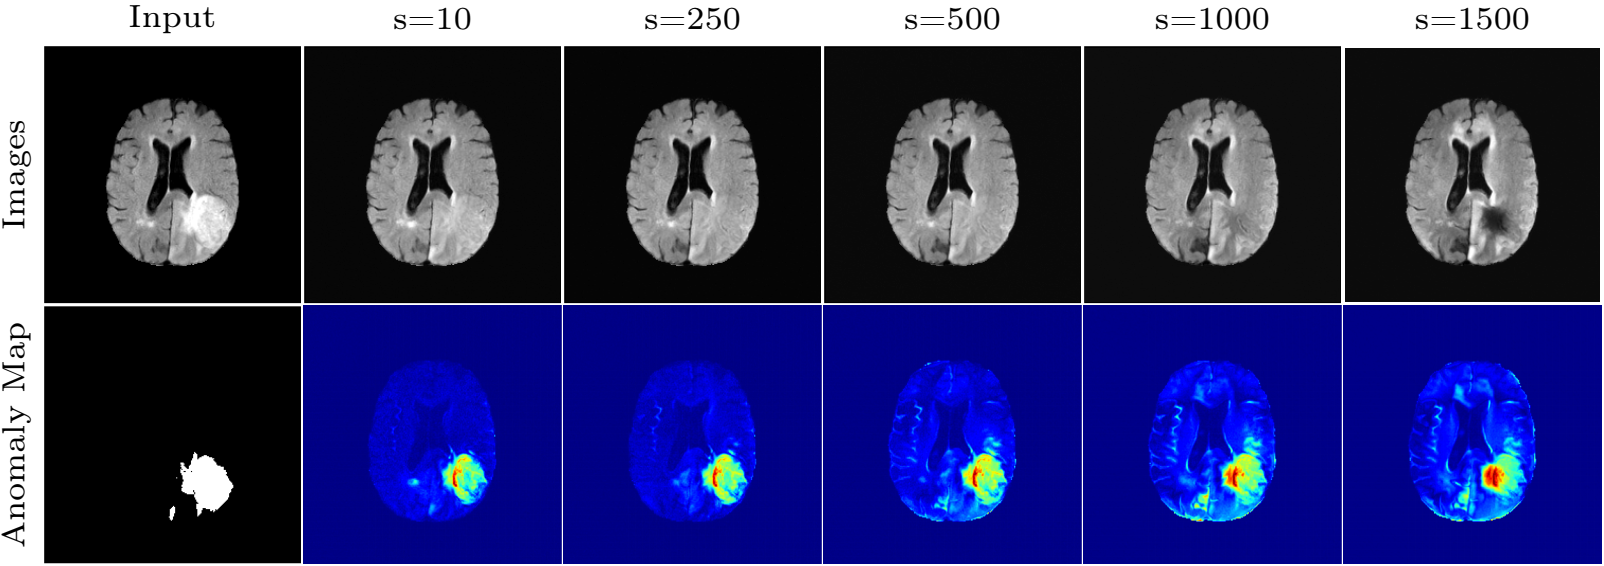

Figure 14. FLAIR image. The sampled results of various s for a fixed L = 500.

Observations:

- s too small: The tumor cannot be removed;

- s too large: Additional artificial features mainly at the border of the brain are introduced. → Dice score↓